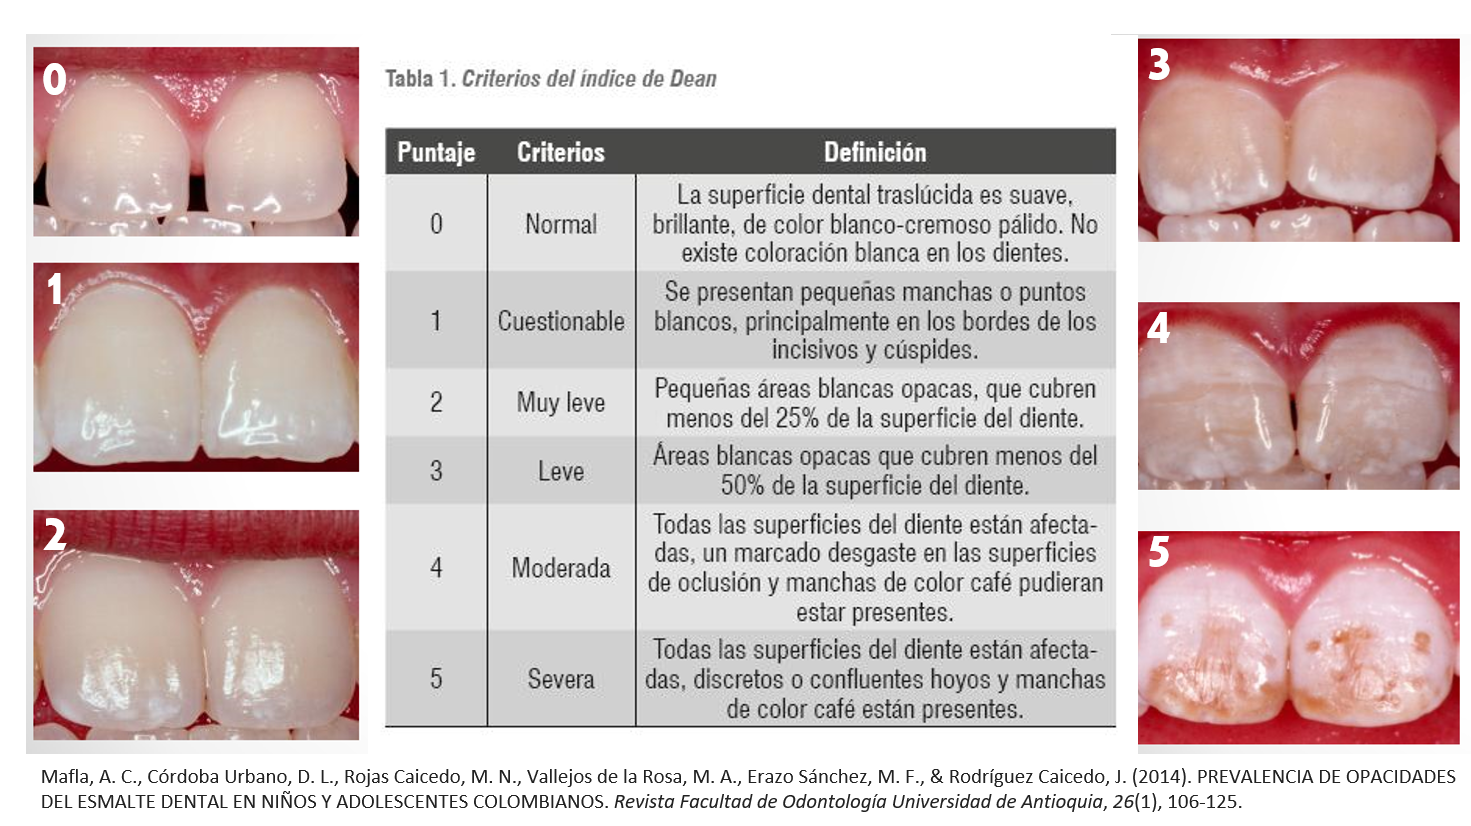

Clasificación de Dean